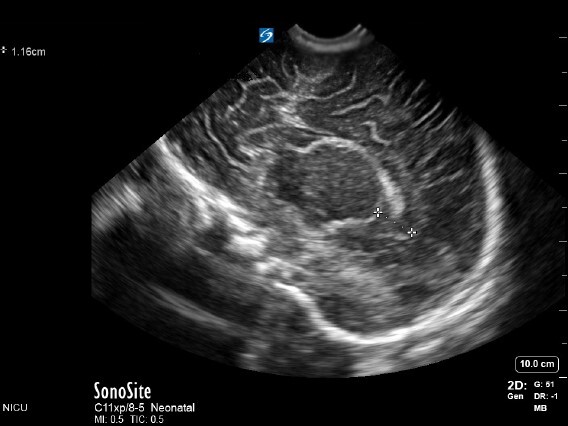

Neonatology TOD 1 Image